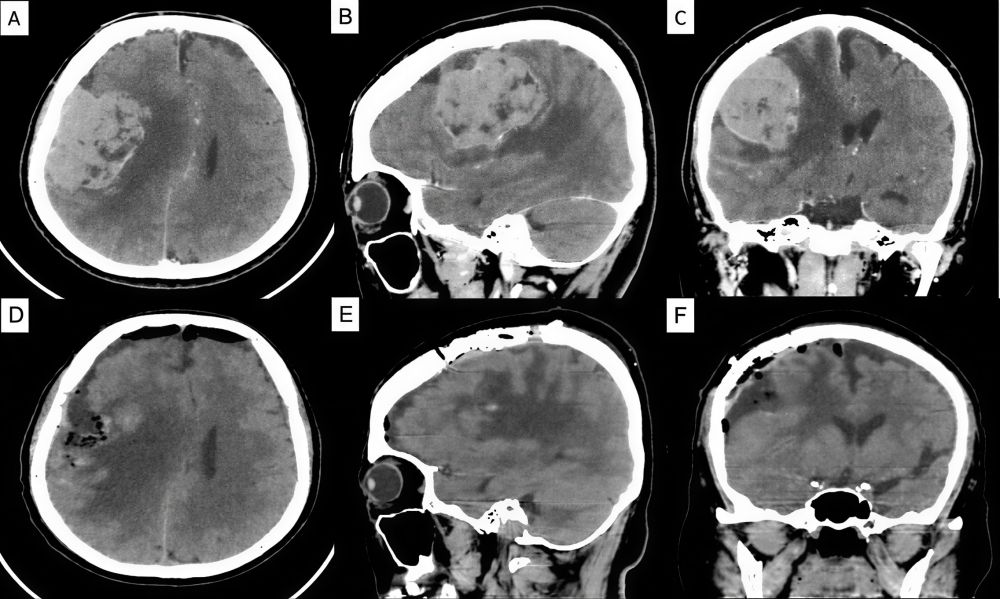

Hình 3. Hình ảnh cắt lớp vi tính sọ não ở các mặt phẳng trước phẫu thuật, với khối u vùng trán-thái dương-đỉnh phải kích thước 7,5x5x5 cm gây hội chứng khối đè đẩy đường giữa sang phải, và hình ảnh cắt lớp vi tính sọ não ở các mặt phẳng axial, sagittal và coronal (D-F) sau phẫu thuật với khối u đã được loại bỏ hoàn toàn.

CT sọ não cho thấy khối choán chỗ vùng thùy trán phải, kích thước 71×50×50 mm, gây phù não lan tỏa và lệch đường giữa 13 mm. Chụp CTA xác định nguồn cấp máu từ nhánh động mạch não giữa phải, các tĩnh mạch vỏ não và xoang dọc trên vẫn lưu thông. Dữ liệu CTA được xử lý bằng phần mềm tái tạo 3D (Horos) giúp xác định mối tương quan giữa khối u, hộp sọ và mạch máu, hỗ trợ lựa chọn vị trí mở sọ tối ưu.

Sau mổ, bệnh nhân tỉnh táo, yếu nhẹ thoáng qua nửa người trái, hồi phục hoàn toàn sau hai tuần. CT kiểm tra xác nhận lấy trọn khối u, đường giữa trở lại bình thường. Giải phẫu bệnh: Meningioma độ I (WHO).